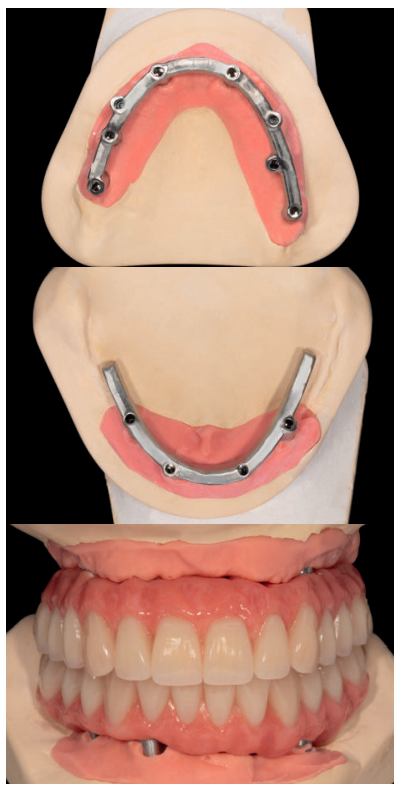

En la misma cirugía de inserción de los implantes se colocan transepiteliales para la carga inmediata, realizándose la misma 24 horas después de la cirugía, debido al uso de barras articuladas que nos facilitan la consecución de la estructura en un tiempo muy bajo, con un correcto ajuste pasivo y hermetismo en la unión transepitelial-prótesis. Los únicos implantes no englobados en la carga inmediata son los más distales del maxilar superior debido a la baja densidad ósea que presentaba el lecho óseo (Figuras 14-16).

Cinco meses después de la confección de la prótesis de carga inmediata se procede a realizar una prótesis de carga progresiva para el maxilar superior, agregando los dos implantes que no se habían cargado en la primera fase (Figura 17).

Con este tipo de prótesis se consigue una carga paulatina sobre los implantes con menor torque y en huesos de baja densidad. Una vez transcurrido un tiempo con estas prótesis podemos elaborar la prótesis definitiva, dándole tiempo también a la oclusión y articulación temporo-mandibular para acomodarse a la nueva dimensión vertical.

Las prótesis definitivas serán realizadas con una estructura por Cad-Cam sobre la que asentarán dos prótesis híbridas. La confección por Cad-Cam de la estructura nos permite además angular las chimeneas de salida para colocarlas en zonas más favorables (para la masticación y para la estética de la prótesis). Para ello se realiza un encerado sobre los cilindros que será probado en boca, para luego trasladar la información de la oclusión obtenida en esa prueba a un escaneado que nos permitirá conocer la posición de los dientes en relación a la posición de la futura barra fresada. El diseño del encerado convencional puede importarse como archivo de imagen y superponerse al diseño tridimensional de la estructura (Figuras 18-23).

Una vez finalizada la confección de la prótesis, se coloca en el paciente. En las imágenes podemos observar el resultado clínico final y la radiografía, donde puede verse el ajuste de las estructuras sobre los implantes (Figuras 24-26).